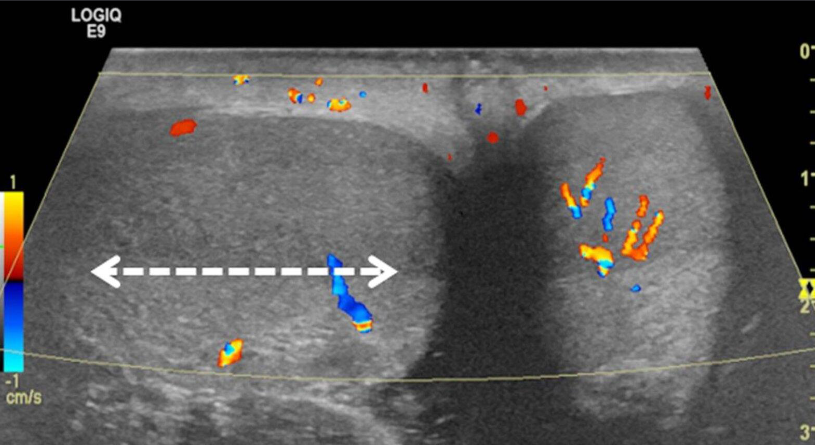

A. Give the name of imaging examination.

Color Doppler ultrasound of both testes (transverse plane) of a 14-year-old boy

B. Describe the abnormality woke up with acute right scrotal pain - The right testis shows intratesticular flow slightly reduced compared to the left testis

C. What is the most probable diagnosis ? These findings are consistent with testicular torsion